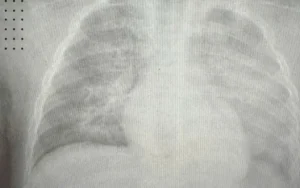

Bé Gái 8 Tháng Nhập Viện Do Biến Chứng Nghiêm Trọng Của Bệnh Sởi

I. Giới thiệu Bài viết sẽ đề cập đến trường hợp đáng tiếc của một bé gái 8 tháng tuổi tại Vĩnh Phúc, bị trắng xóa phổi do biến chứng nặng nề từ bệnh sởi. Tình trạng sức khỏe của bé đã trở nên nghiêm trọng...